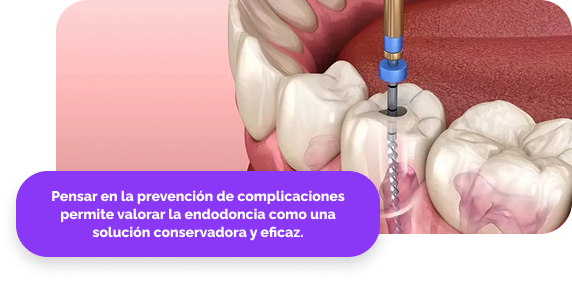

🪥 Prevención de infecciones y complicaciones mayores

Un tratamiento de endodoncia oportuno elimina bacterias del interior del diente y evita que la infección se propague al hueso o a otras zonas de la boca, preservando la estructura dental y la función masticatoria.